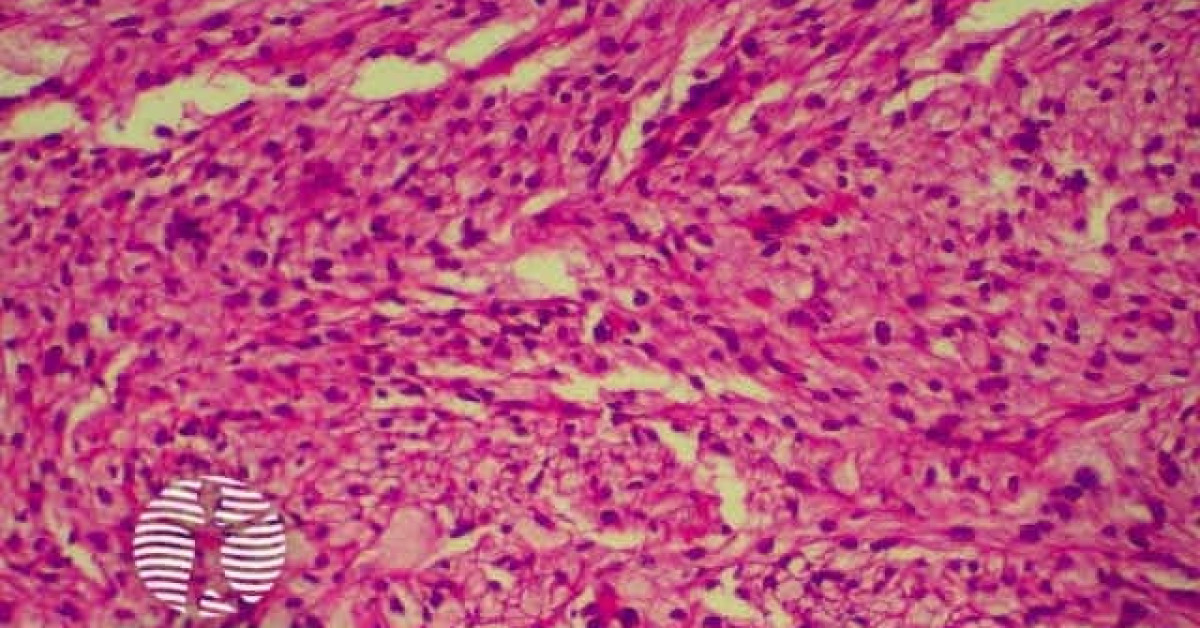

Atypical fibroxanthoma (AFX) is frequently found to have a well-circumscribed, nonencapsulated dermal tumor that is either contiguous with the epidermis or separated from it by a narrow zone of collagen (Grenz zone); plump spindle cells with prominent nuclei, epithelioid cells, and multinucleated giant cells; atypical mitoses and severe cellular pleomorphism; and varying presence of thin or ulcerated epidermis or peripheral epidermal collarette.